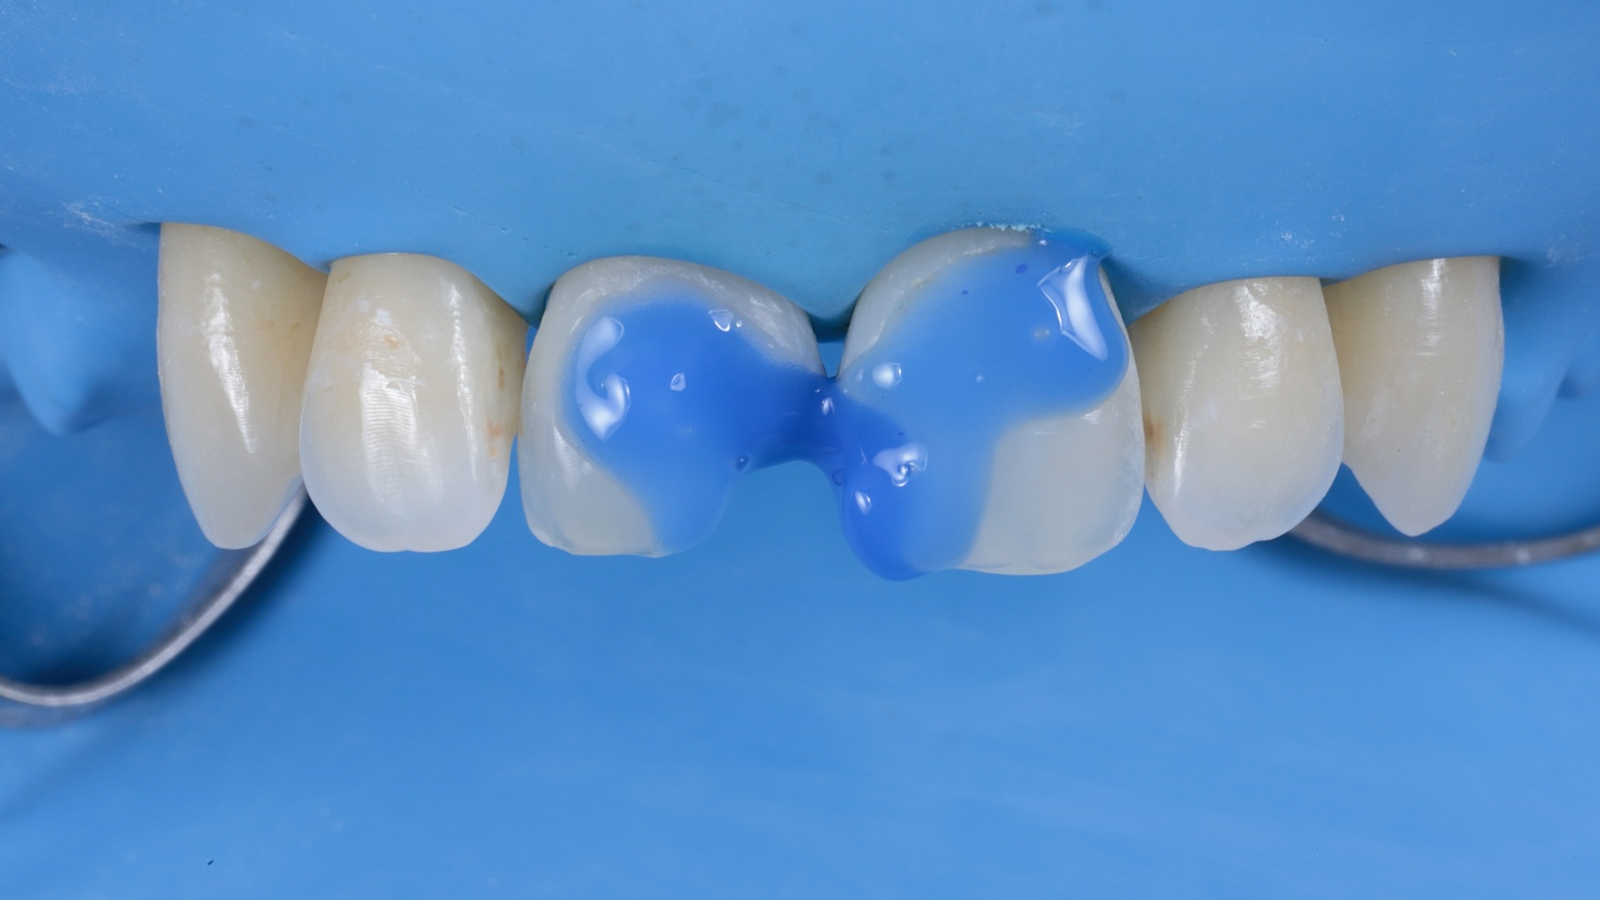

The teeth were etched with 35% orthophosphoric acid and bonded using iBOND Universal (Kulzer).

Venus Pearl MEDIUM was used to reconstruct the teeth in a single-shade layering technique. This approach can speed up the restorative procedure and significantly shorten the treatment time.